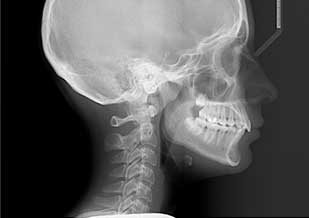

Telerradiografía lateral de cráneo

Estudio extra oral que ofrece una visión lateral de las estructuras de interés, resulta imprescindible para un correcto diagnóstico ortodóntico y en cirugía ortognática.